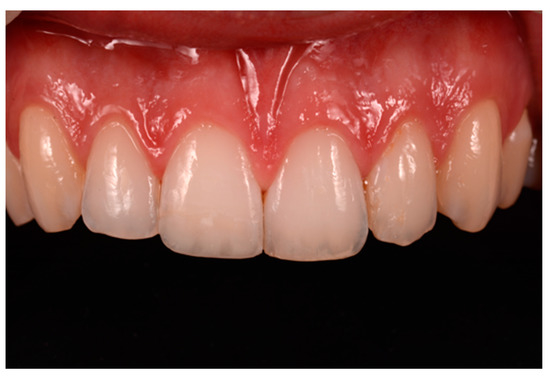

Figure 47.

Six months post-operative.